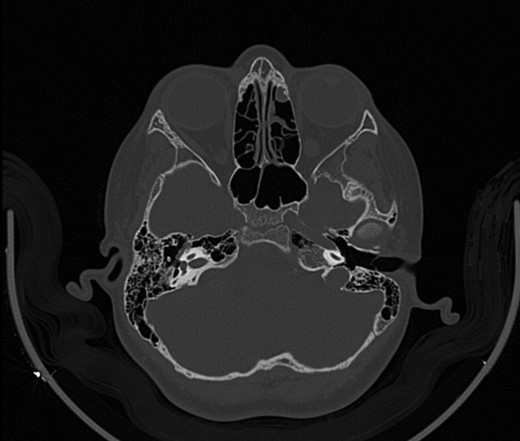

A 14-year-old male patient presented to the ENT clinic with bilateral hearing loss with no other otolaryngological symptoms. History from the patient stated a road traffic accident (RTA) 12 months ago. Meanwhile, the patient had no hearing problems prior to the RTA. Furthermore, detailed history of the accident revealed that the patient had no apparent skull injuries while pure tone audiometry (PTA) on presentation revealed bilateral conductive hearing loss and auditory brainstem response revealed right mild hearing loss and left moderate hearing loss. As a result, he was fitted with hearing aid for four months after presentation and was not compliant to it on the long-term. The patient is a non-smoker and is medically free with normal developmental milestones and negative family history of hearing complaints. Local examination of the ear revealed intact but minimally retracted tympanic membrane bilaterally. PTA was done in 2014 revealed right mild to moderate mixed hearing loss and conductive hearing loss at low frequency (Table 1). Meanwhile, the left ear had mild to moderate sensory hearing loss at high frequency (Table 2). The speech audiogram results show equal canal volume in both ears, less tympanometry pressure on the right ear and less compliance on the right ear (Table 3). The CT showed that both ossicular chains are deranged, and bilateral abnormal ossicles with no fracture or mass (Figures 1–3).

Figure 1:

CT mastoid, deranged right side ossicular disruption.

Figure 2: